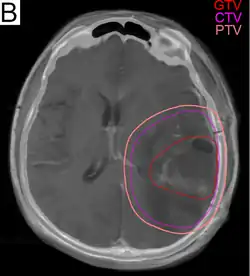

.png)

Glioblastome werden, etwa vier Wochen nach einer ggf. stattfindenden Operation, in der Regel mit einer Gesamtdosis von 60 Gray in etwa 30 Sitzungen bestrahlt. Bei höherem Patientenalter und/oder schlechter Prognose können auch Therapiepläne mit geringerer Gesamtdosis zum Einsatz kommen. Besondere Bestrahlungsverfahren, Brachytherapie oder Radiochirurgie bieten keinen Überlebensvorteil gegenüber der Standardtherapie.[16][23]